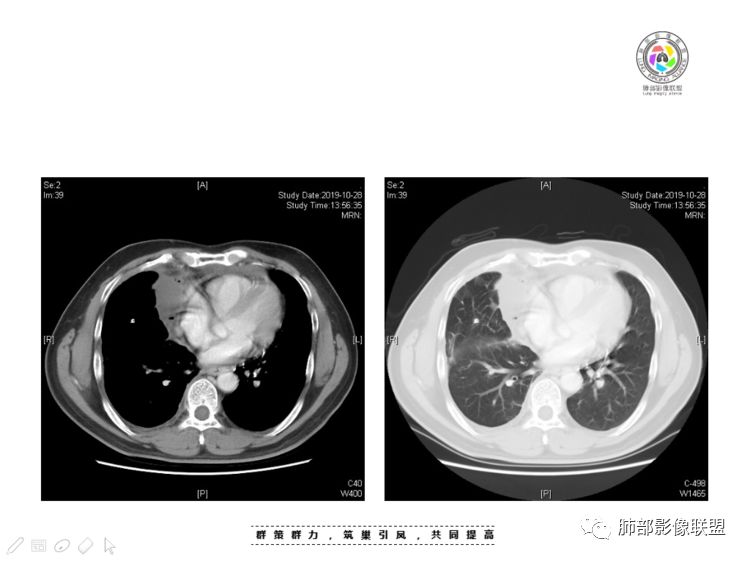

南边:大家看看前纵隔的病灶,符合肿瘤吗脂肪,周围密度增高

三个石头:比较散;像炎症的蔓延生长南边:是,这些看着心里不踏实觉得把这个纳入肿瘤去考虑是否合适总觉得边缘收缩的、散在的朝周围蔓延;中央还跨过脂肪,朝对侧胸膜蔓延把这个与囊性病变连到一起去考虑是否还需要斟酌一下因为这个就方向差异大了南边:连在一起,囊实性,边界不清,自然考虑恶性:如果独立,囊张力高、边界清楚,间隔,自然朝良性考虑:

南边:我总觉得这个纵隔内不像是一个肿块的改变,扁平,周围蔓延:有符合炎性的的特点,或者肿瘤的侵犯;但是肿瘤的侵犯,不大符合,实性部位的边缘过于柔和,没有毛糙的侵犯边缘。

如果前纵隔淋巴瘤,囊在中央,周围大量实性才对